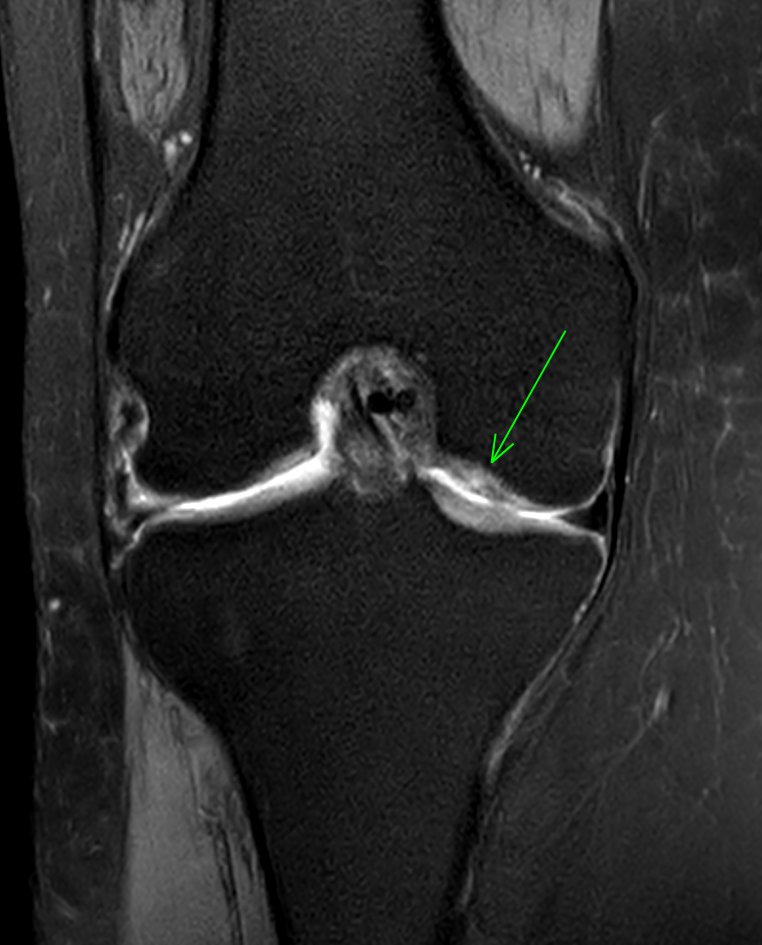

JuanMiranda@themskarchive·

19/11/2025. 🦵 55 y/o woman with knee pain. FSPD #MRI, 1 year apart: 📍 Baseline: large osteochondral defect in the lateral aspect of the medial femoral condyle 🔧 Arthroscopic microperforations (microfracture) ✨ Follow-up: defect filled with fibrocartilage-like tissue👀 #MSK

JuanMiranda tweet mediaJuanMiranda tweet mediaJuanMiranda tweet mediaJuanMiranda tweet media